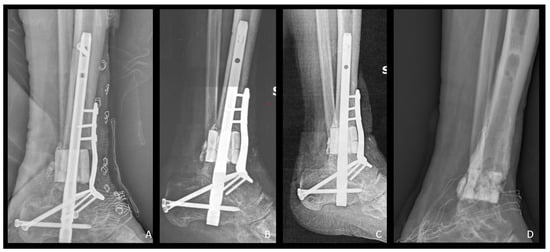

Figure 2.

Lateral view X-Rays representing radiological follow-up of the same patient as in Figure 1. (A) Postoperative X-Ray showing b.Bone™ cylinder application. Fixation was achieved through a retrograde ankle fusion nail and an anterior plate; (B–D) follow-up at 6, 12, and 23 months after the surgery. Note: in (D), b.Bone™ integration and stability even after hardware removal.